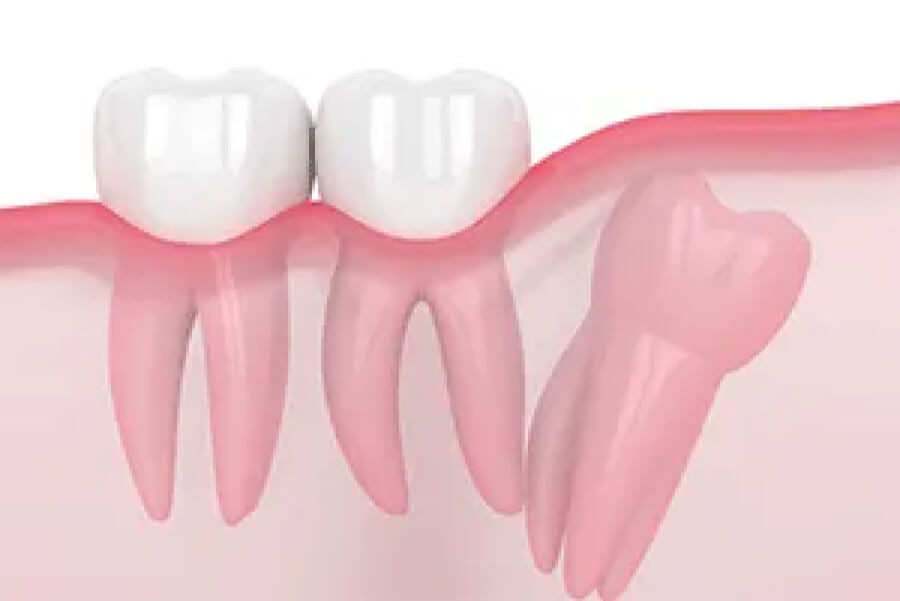

難しい親知らずの抜歯も対応可能 あなたの親知らずはどんな生え方ですか?

親知らずの状態によって、抜歯しなくても良いケースや痛みがなくとも横向きに生えており抜いた方が良いケースなどさまざまです。千賀デンタルには、口腔外科に特化した専門ドクターが常駐しておりますので、年中無休で親知らずの抜歯が可能です。また、他院で断られた難症例のケースでも大学病院へ行かずとも処置が可能ですので、まずは一度ご相談くださいませ。

• 斜め、真横に

生えている

斜め、真横に生えている